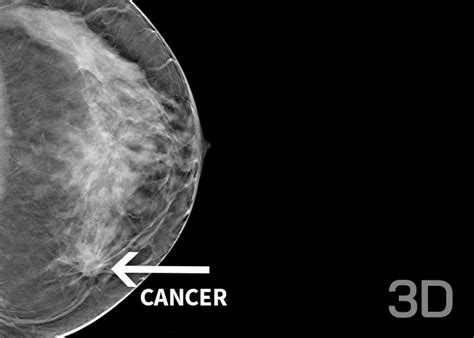

Senologie

Controlul mamografic, specific vârstei, este cea mai eficientă metodă de a depista cancerul de sân precoce. Clinica Nativia dispune de tehnologie avansată pentru asigurarea unei îngrijiri de înaltă calitate, pentru siguranța și confortul pacientelor și diagnostic de precizie.